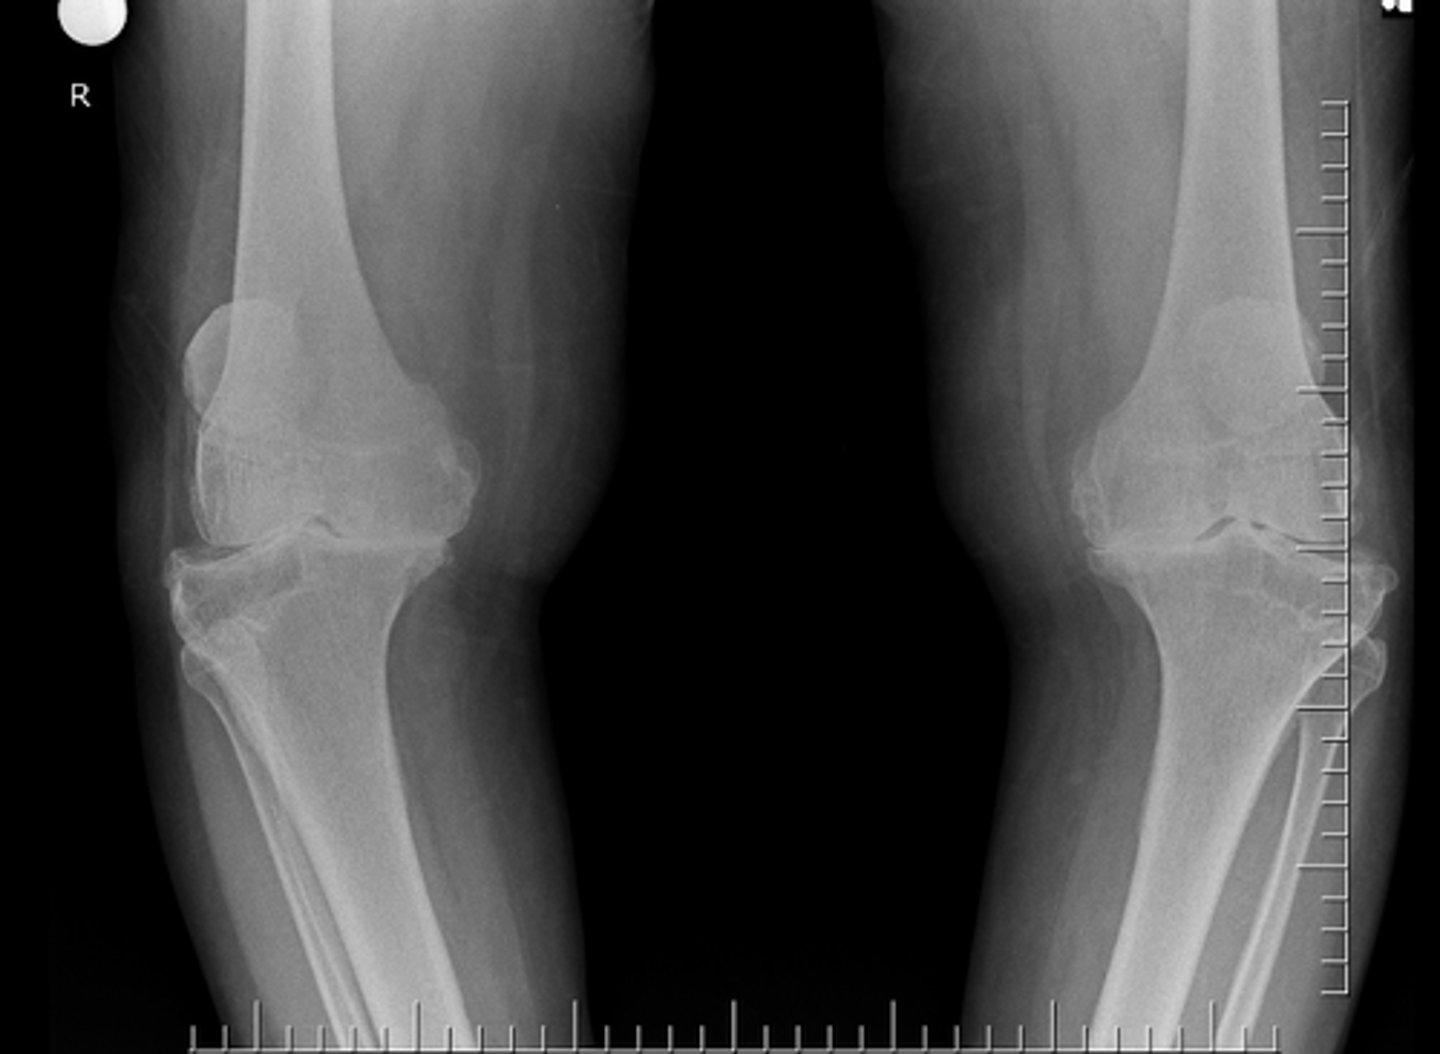

- Subluxation

- Non-uniform loss of joint space (medial tibiofemoral joint)

- Osteophytes

- Subchondral sclerosis

Describe findings

Osteoarthrosis

Diagnosis?

Genu varum

Clinically, the patient's lower extremities would take on what kind of appearance?